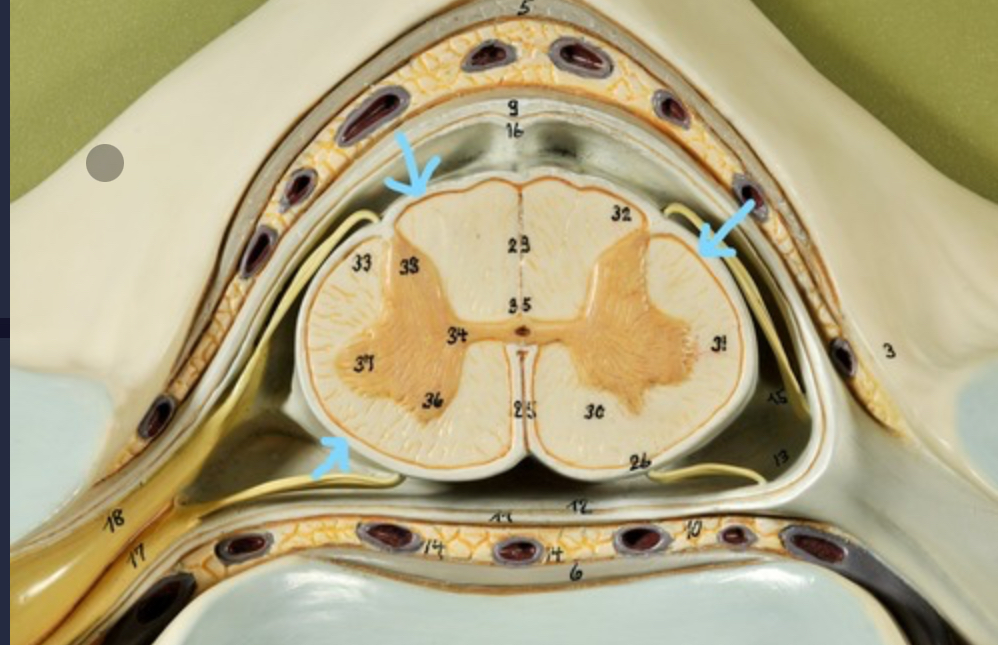

Dura mater (outermost layer)

White matter of spinal cord

Gray matter of spinal cord

Ventral horns (of gray matter)

Lateral horns

Dorsal horns

Anterior columns of white matter

Lateral columns of white matter

Posterior columns of white matter

central canal of spinal cord

Pia matter

Subarachnoid space

Arachnoid matter

Subdural space (brown line)

Dura matter

Epidural space

Dorsal root ganglion

Dorsal root

Ventral root

Spinal nerve